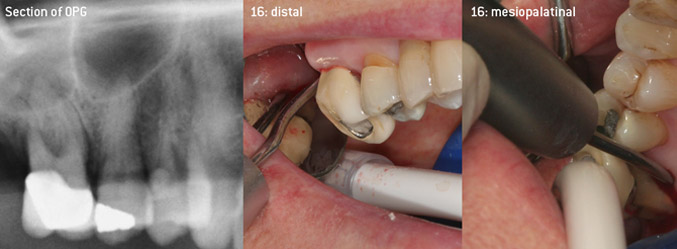

Open debridement of the furcations on teeth 16 and 17

Fig. 3: Open debridement of the furcations on teeth 16 and 17 in case of advanced attachment loss

As initiators of the development of the new diamond-coated 3AP air scaler tip, the two dentists recognized the need for improvement of the handling restrictions of the commercially available diamond-coated tips, especially during furcation treatment and when working in tight intraosseous pockets. This should be possible for both non-surgical (Figure 2) and surgical (Figure 3) procedures.

The aim was to develop a universally applicable tip in order to avoid time-consuming tip changes. In addition, it should be easier to use the new working tips in tight intraosseous pockets from distal and at the distal furcation entrance of maxillary molars, allowing more effective use of instruments as a result. This was achieved by employing an instrument curve with a larger diameter (Figure 1), which is highly advantageous for closed debridement on teeth with advanced attachment loss and involvement of furcation in particular (Figure 4).